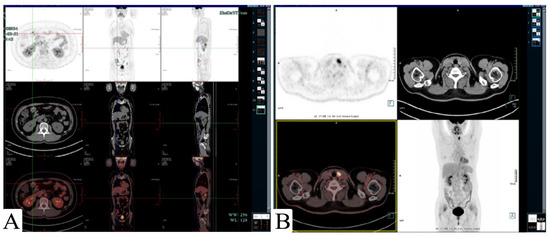

2. Case Presentation